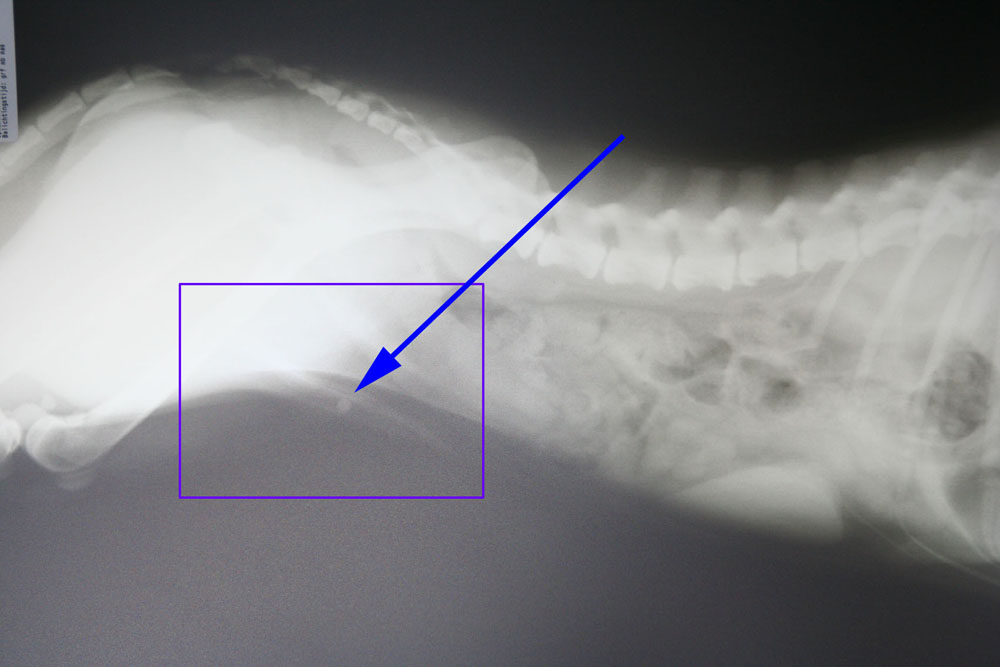

Hierna hebben we een urinekatheter ingebracht die na 4 cm vastliep op een harde structuur. Op de röntgenfoto is er bij de pijl een blaassteen te zien die vastgelopen is in het penisbotje.

Na verder onderzoek verricht te hebben kwamen we tot de conclusie dat er in de blaas zelf nog wat gruis zat en mogelijk zeer kleine steentjes.